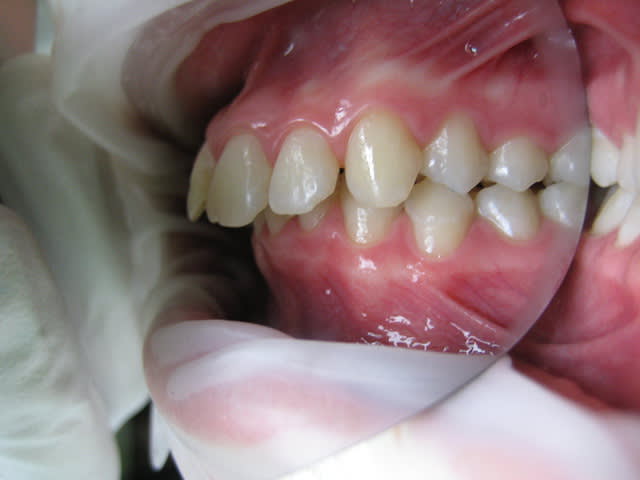

J'ai une patiente de 14 ans qui présente une full classe II due à un maxillaire en proposition car sur une base du crâne trop longue en antérieur. Le maxillaire a une longueur normale.

Voici les photos, radios et moulages du cas

Le maxillaire n'est pas si avancé que cela, par rapport a mac namara ( mais c'est normale, si c'est la base du crane qui est augmenté ) : donc : chirurgie pour raccourcir la base du crane ?

La mandibule semble un peu en retrait, au niveau profil : peut-etre encore possible de mettre un propulseur type PUL, mais à 14 ans pour une fille, c'est limite.